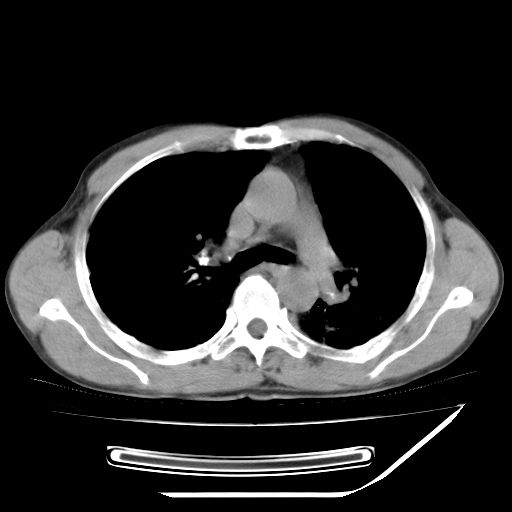

男,59岁,“结核性胸膜炎”30余年,胸部经常疼痛,多次x检查提示“肺部”炎症。腹部疼痛5日,b超提示:“肝内短管结石,余显示不清,建议进一步检查。”

两肺结核并右侧胸腔积液;脾脏、腹腔及腹膜后淋巴结结核[陈旧性];肝内胆管结石

胸部腹部都是结核(双肺。纵隔淋巴结,肝脏,脾脏,肠系膜)

均为结核所致,右侧少量胸腔积液